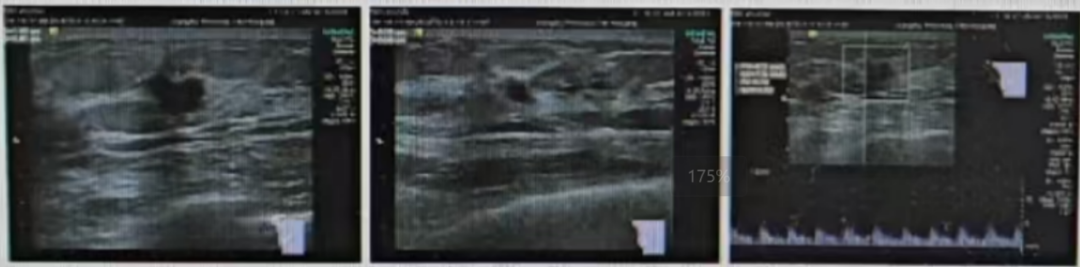

·CT

1、右乳后上方结节影,伴右侧腋下多枚淋巴结,建议乳腺核磁MRI平扫+增强进一步检查;

2、右肺下叶及左肺下叶胸膜下少许间质增生,或可能由肺坠积效应所致;

3、肝脏钙化灶

4、胸腰椎轻度退行性变。

图4 CT结果